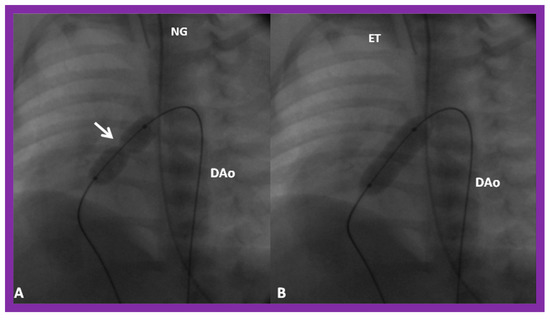

3.3. Aortic Coarctation, Native

4.3. Aortic Coarctation–Native

Revisit BA in the Neonate and Young Infant